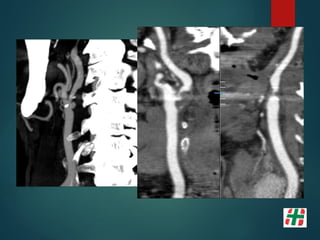

Paciente mujer 56 años, fumadora.

Episodios repetidos de déficit

transitorios en ambos hemicuerpo,

mayormente del lado derecho.